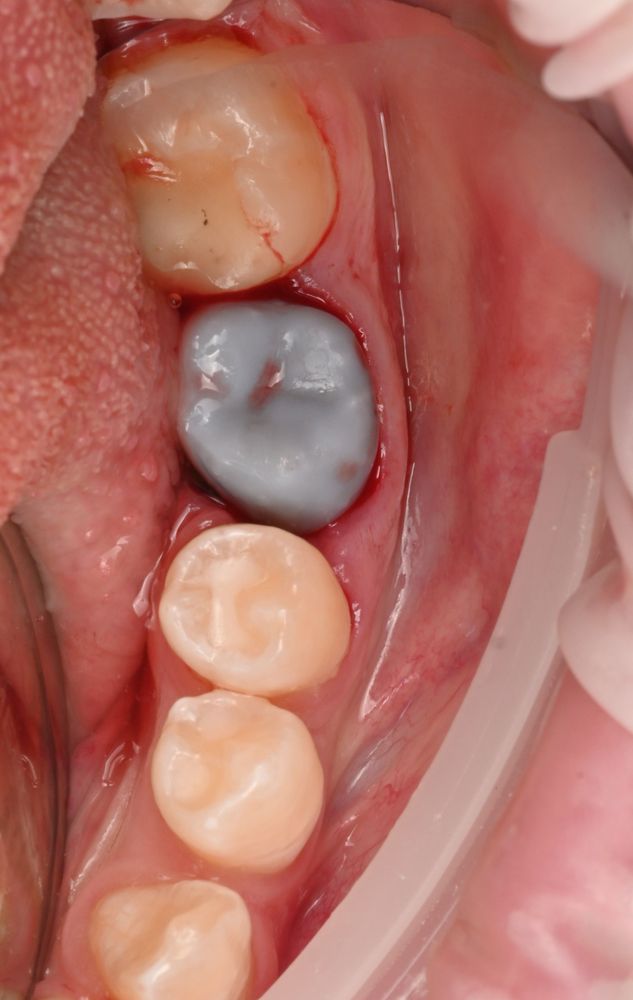

После подготовки мы пересадили зуб мудрости и зафиксировали его тонкой шиной.

Через 20 дней шину сняли — зуб хорошо прижился. Спустя два месяца он уже полноценно участвовал в жевании, а снимки показывали стабильную и правильную адаптацию.